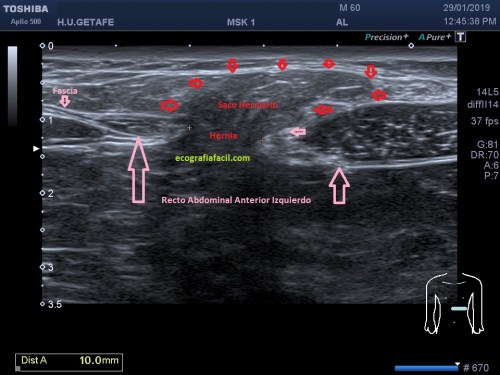

Si tu lo quieres estudiar en un corte transverso o eje corto del tendón verás como muestra de normalidad la imagen número 1. Semiológicamente es muy agradecido. Ves el tendón ovalado, hiperecogénico reposado en la corredera bicipital. El ligamento transverso humeral, hiperecogénico y lineal, anterior a la estructura tendinosa que descansa en la corredera.